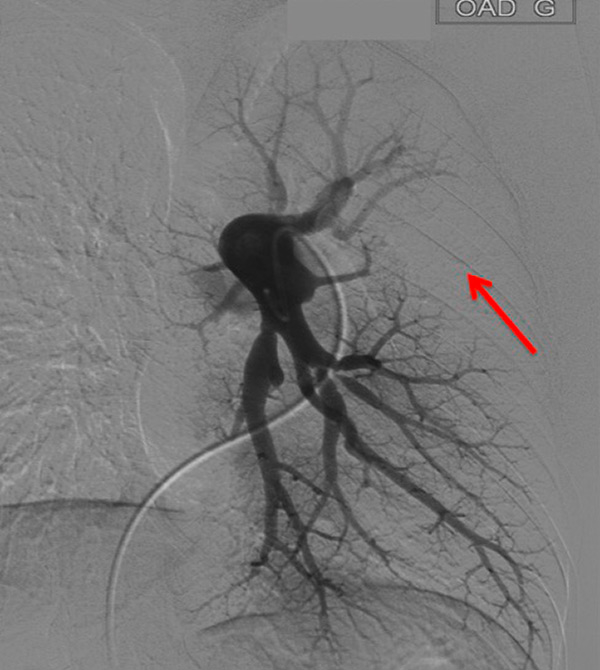

Figure 3

Chronic thromboembolic pulmonary hypertension (CTEPH). Segmental occlusions of pulmonary arteries (arrow) in the pulmonary angiography (A) are clearly visible on the CT angiography (B), with normal lung (C), and responsible for triangular perfusion defects (arrows) on the perfusion maps (D) confirmed by the ventilation-perfusion scintigraphy (E–F).